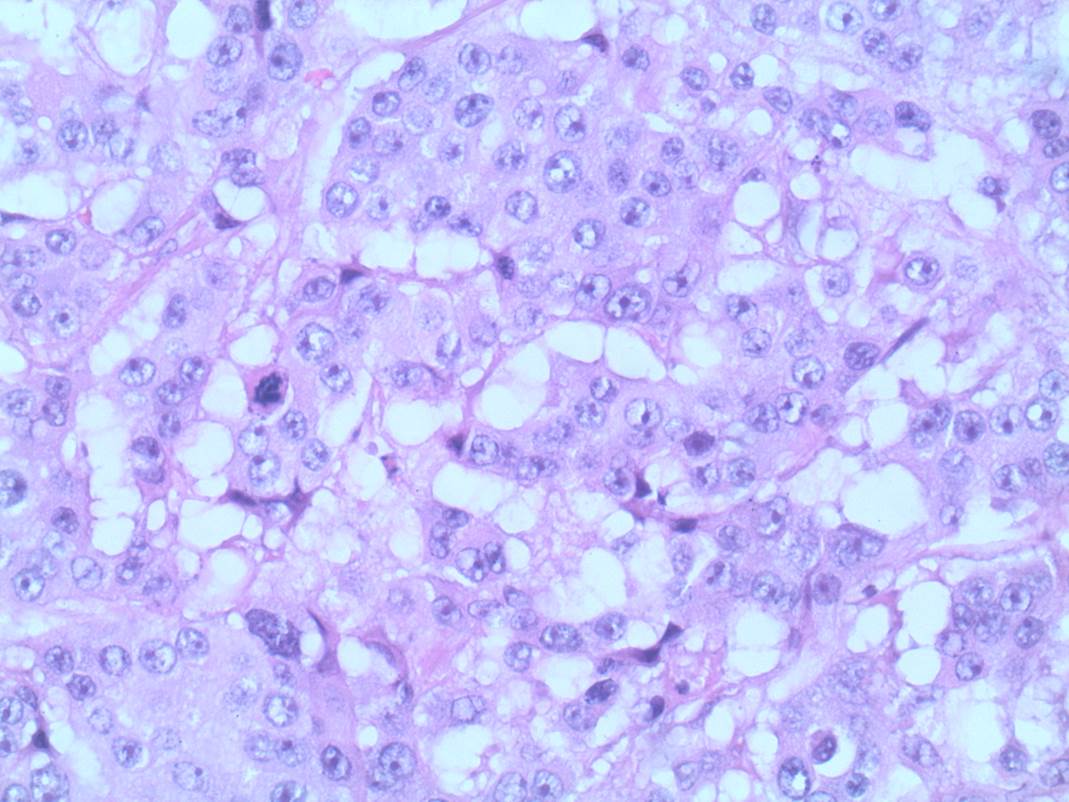

Invasive carcinoma is most commonly ductal carcinoma of no special type, with invasive lobular carcinoma the next most common. Invasive lobular carcinoma may show more extensive disease than appreciated clinically, or on imaging pre-operatively, and it is useful for this identification to assist with planning surgery. Tumour grade is a measure of tumour differentiation and is an important prognostic variable that influences decisions about additional treatment such as chemotherapy. Grading takes into account the ability of the tumour to make glands, the degree of nuclear pleomorphism and the proliferative rate measured by counting mitoses (Figure 1 – grade 1 invasive carcinoma, Figure 2 – grade 3 invasive carcinoma).

![This image depicts grade 1 invasive carcinoma. Professional medical imaging for clinical reference and educational purposes. [umbracoNodeId=9796]](/assets/image/jpeg/grade-1-invasive-carcinoma-388flzbxollwtxxzypol0i.jpg)

Figure 1: Grade 1 invasive carcinoma